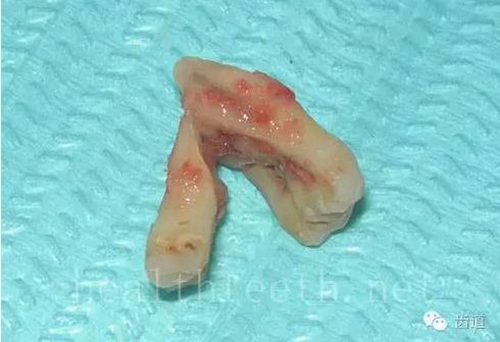

牙冠劈裂及完整拔除后的情況

63.jpg

64.jpg

牙根縱裂及拔除后的情況